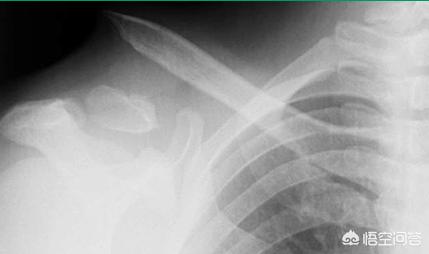

3、“8”字绷带固定法

对于大部分单纯锁骨骨折患者来说,此类固定方法有效果。但是要注意,带着非常痛苦!!!

但注意:对于伴有锁骨周围韧带损伤,失去韧带保护的锁骨骨折来说,避免使用“8”字绷带固定法,因为不能支撑手臂的重量,有可能会加重骨折移位,需要大家注意!(如下图)